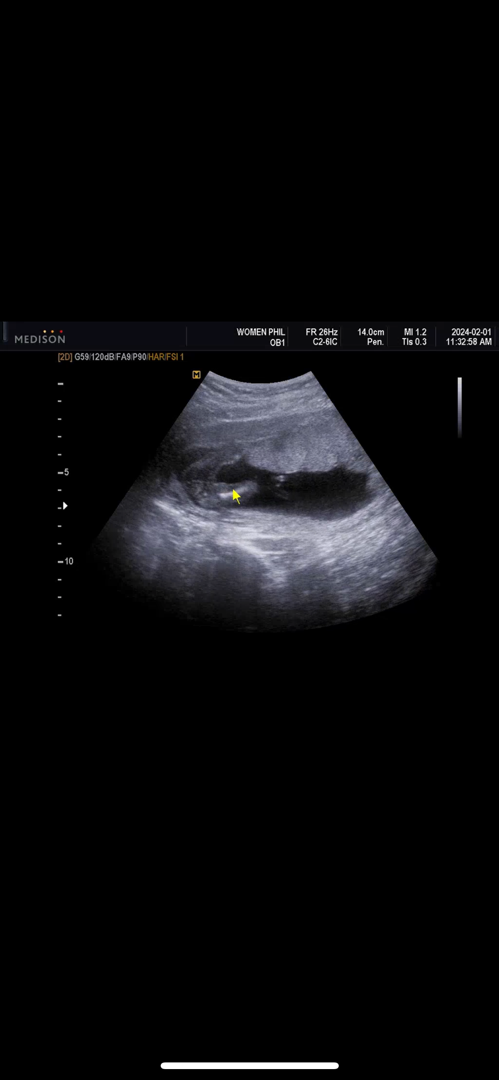

오늘 16주라 2차 기형아검사라서 보고왔는데 신랑도 저도 미사일은 전혀 안보이고 선생님도 엄마닮았다고 하시는데.. 20주에 과연 반전이 생길까요😁😁

크크 애기아빠도 저도 아들을 약간 더 원했던지라.. 그래도 좋네요 너무 건강해서 마음 편해요